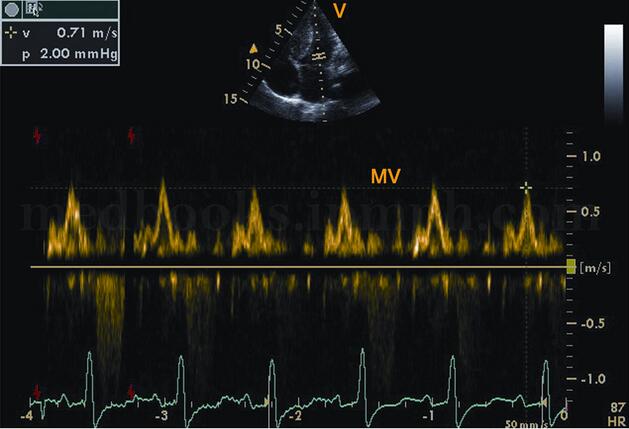

(2)二尖瓣口血流频谱异常的形态随疾病时期和程度不同,表现形式各异。①早期:A峰增高,E峰减低,E/A<1.0(图2‐1‐191)。②中期:呈“假性正常化”,二尖瓣E峰正常或稍增高,A峰减低,E/A>1.0(见图2‐1‐192)。DTI可以帮助鉴别这种“假性正常化”。③晚期:“限制性”充盈,E峰呈高耸的尖峰波,A峰极低或消失,E/A>1.5~2.0(图2‐1‐193)。

图2‐1‐191 二尖瓣口血流频谱:病变早期表现为A峰增高、E峰减低,E/A<1.0